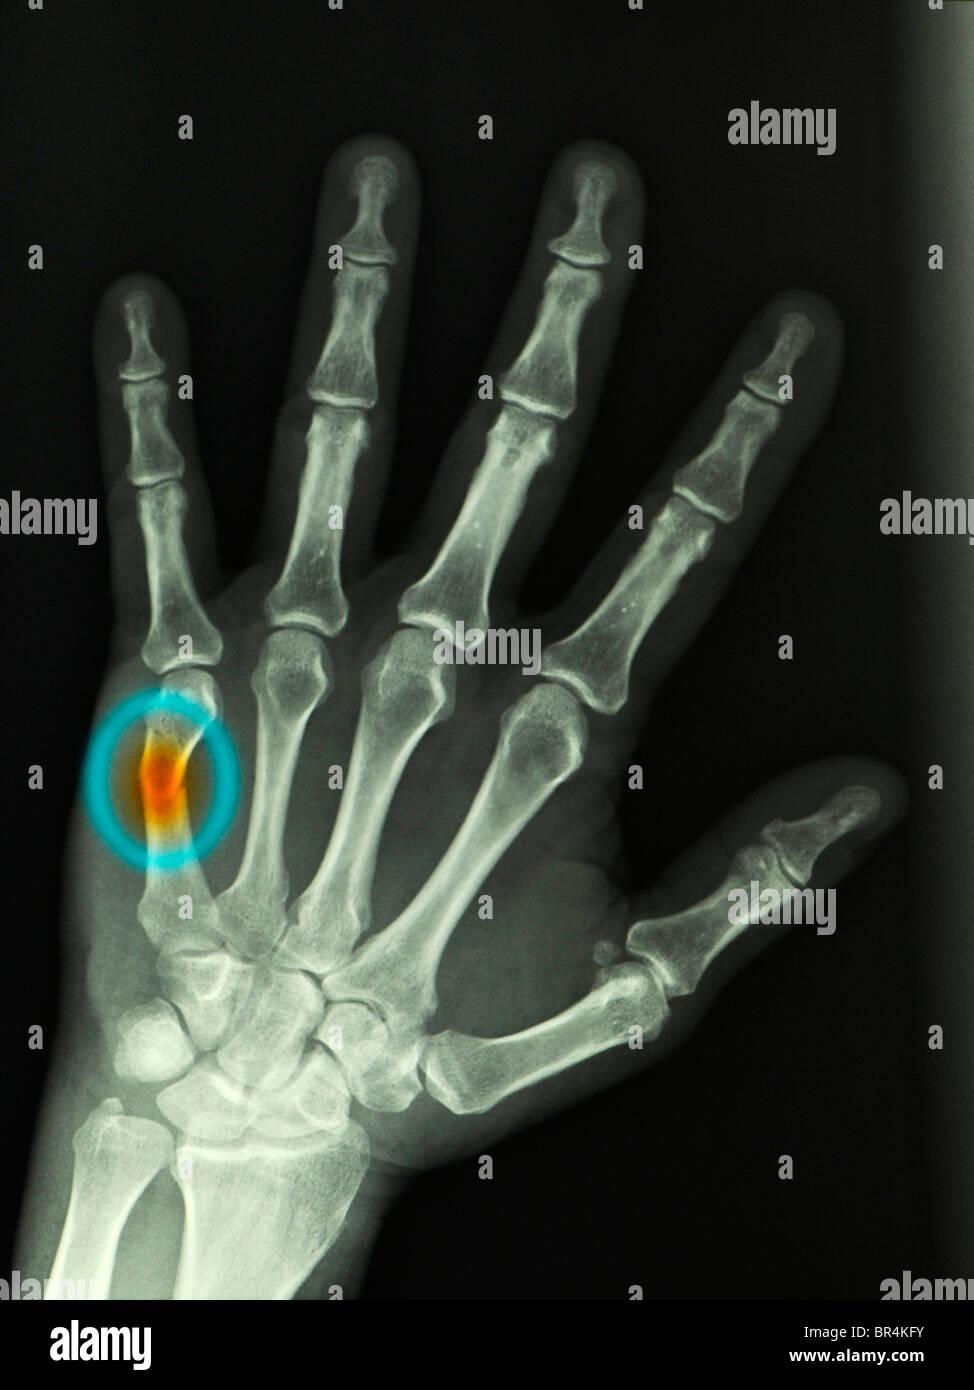

Sore Hand From Punching Wall . If you’re experiencing hand pain after hitting a wall, it’s essential that you get it checked out by a doctor. Do you have hand pain after punching a wall? One of the most common injuries associated with punching a wall is hand pain. One of the most common injuries after punching a wall is hand pain. A boxer’s fracture is a fracture (broken bone) of the hand. More specifically, it is a fracture of the neck of the fifth metacarpal (a bone in the “pinky finger). It could be a boxer’s fracture. In today’s blog, we’ll look at what causes this pain, and why it’s important to get it treated by an orthopedic surgeon, particularly if. Here are 4 signs that you may have a boxer’s fracture: Boxer’s fracture are very common hand injuries. It’s important to note that you may be experiencing some of the symptoms above. Punching or hitting something hard with a closed fist (like punching a wall in frustration) is the most common cause of boxer’s fractures. The typical symptoms of a boxer's fracture are pain or tenderness on the hand near one of the metacarpal bones, around the knuckle.

Pain in the Hand After Punching a Wall Journal of Urgent Care Medicine Sore Hand From Punching Wall The typical symptoms of a boxer's fracture are pain or tenderness on the hand near one of the metacarpal bones, around the knuckle. Boxer’s fracture are very common hand injuries. One of the most common injuries after punching a wall is hand pain. A boxer’s fracture is a fracture (broken bone) of the hand. It could be a boxer’s fracture.. Sore Hand From Punching Wall.